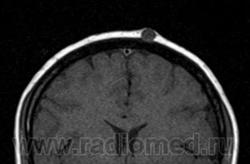

Клинически пиломатриксома представляет собой узел шаровидной или шальной формы, хорошо пальпируемый под поверхностью кожи. Характерная особенность этой опухоли - ее плотная консистенция. Опухоль не спаяна с окружающими тканями, подвижна, иногда умеренно болезненна при пальпации. Обычный размер новообразования 0,5-3 см и более. В начале заболевания расположенный в глубоких слоях кожи опухолевый очаг больших размеров практически не заметен и не вызывает никаких субъективных ощущений у пациента. С течением времени, постепенно увеличиваясь в размepax, опухоль начинает выбухать над поверхностью кожи, которая иногда выглядит истонченной, атрофичной, гиперемированной, может шелушиться и порываться коркой (изредка встречаются пигментные формы). Больные начинают предъявлять жалобы на гуд, жжение, покалывание и (чаще всего при локализации на лице) на онемение.

Клинически злокачественная пиломатриксома представляет собой узел диаметром от 1 до 20 см (в среднем 4 см). Его консистенция в зависимости от степени кальцификации опухолевых тканей варьирует от мягкой до плотной. Опухоль обычно располагается на голове и шее (57%). Наиболее частые локализации, в порядке убывания: шея, околоушные и поза-диушные поверхности, волосистая часть головы. Изредка описывают злокачественные пиломатриксомы грудной клетки (13%), спины (11%), верхних (10%) и нижних (9%) конечностей. У детей опухоль также преимущественно (в 50% случаев) располагается на голове и шее, но ее диаметр меньше (в среднем 2 см), а максимальный размер не превышает 4см.